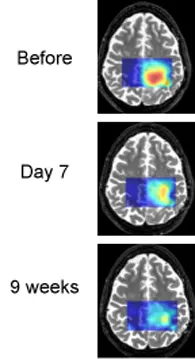

Tumor cells often produce an excess of lactic acid. MRS brain scans show that lactic acid levels are decreasing as treatment proceeds. This patient is an example of a "good responder."

In this National Cancer Institute (NCI)-sponsored clinical trial, the researchers are using magnetic resonance spectroscopy (MRS) to detect changes in brain metabolism brought on by vorinostat. MRS, a form of imaging similar to MRI, allows doctors to monitor the levels of several brain chemicals. The researchers will gauge the levels of inositol and N-acetylaspartate, which are both indicators of healthy brain metabolism.